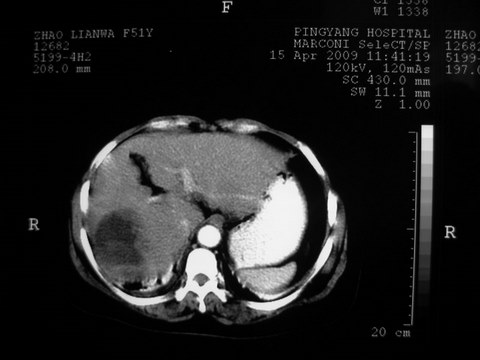

患者 女 51岁 两天前感觉上腹疼,无明显诱因,b超示肝右叶囊实性占位,边缘清楚,其内回声不均匀,ct增强如图,大家看看是什么 ,病人一年前及两月前b超检查只是提示胆囊炎

外院术后,证实肝癌合并出血

特点:1,病灶发展迅速,(2月前正常)[br] 2,囊实性,且并边界清晰光滑,呈右后叶赘生性。囊性区无强化,实性部分较多轻度强化,边界欠清。考虑囊腺癌或囊腺瘤。

增强扫描好像都没有强化的,不管灶周还是灶中心,支持考虑包虫病,别不除外肝囊内内出血,那些一块一块的为血凝块

出病理 中分化肝细胞癌合并出血